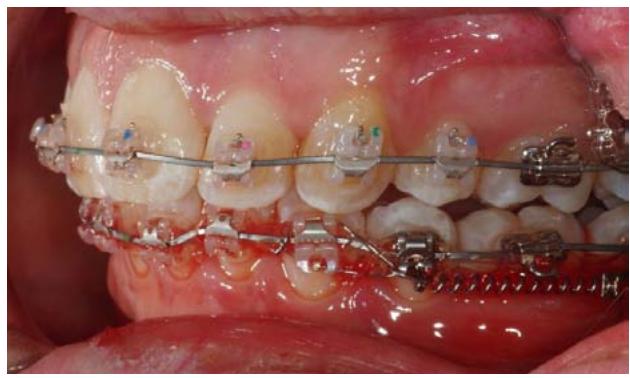

L'ancrage est mis en traction par un ressort NiTi de 300 grammes mis en place de façon simple après l'intervention. L'extrémité postérieure du ressort NiTi est fixée sur la partie toronnée du fil d'osteosynthèse.

L'extrémité antérieure du ressort est connectée à l'appareil multi bagues inférieur par une ligature métallique. Il s'agit dans ce cas d'une traction directe.

Dans le cas de notre paciente, la distalisation débute sur un arc à mémoire de forme de section.020 x.020.

Vue du système de traction du côté droit, gauche, puis en vue occlusale.